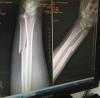

Прикрепил, что есть.

Является ли этот перелом поперечным или косым?

Интаоперационно выявлен многооскольчатый характер перелома.

Можно ли по этим снимкам утверждать категорически, что перелом от ударного воздействия ногой?

См.выше. Из того, что видно: косо-поперечный перелом.

Это характерно для ударного воздействия.

Нет. По этим снимкам невозможно установить идентифицирующие особенности следообразующей поверхности травомобразующего предмета. Однако, учитывая характер повреждения, принимая во внимание известные из специальной литературы и медицинской практики свойства ноги, как травмирующего предмета, не исключается возможность формирования перелома от удара ногой.